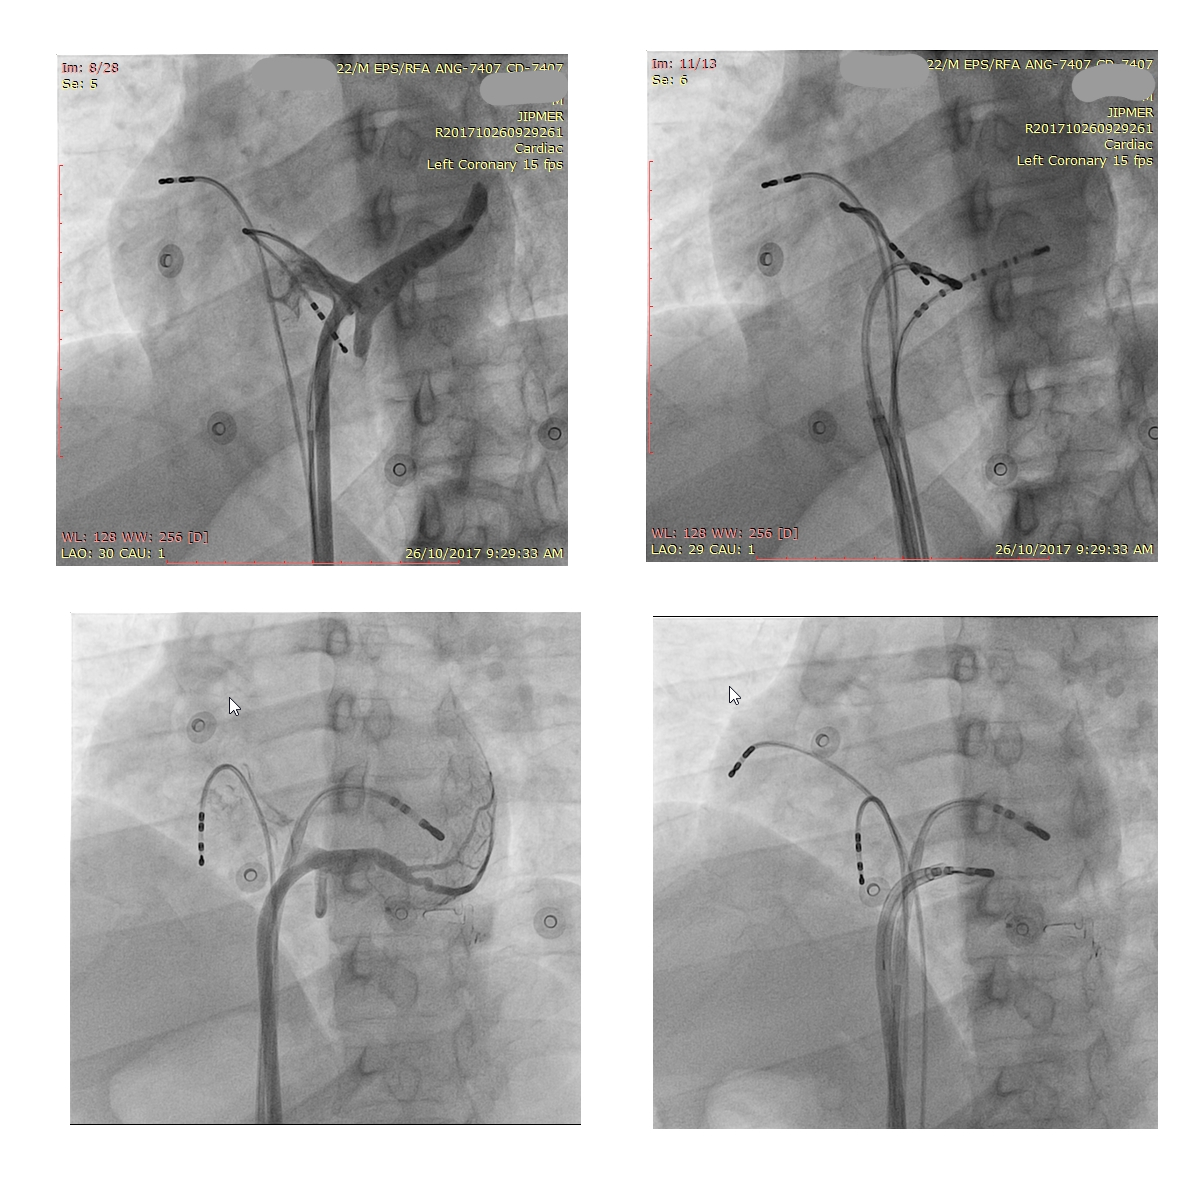

CS diverticulum

ecg.jpg

Mapping in diverticulum

diverticulum.jpg

med_lat_div.jpg

signals.jpg

Mapping in diverticulum - CSE potential most important

div_schematic.jpg

Selvaraj RJ et al. Radiofrequency ablation of posteroseptal accessory pathways associated with coronary sinus diverticula. J Interv Card Electrophysiol. 2016 Nov;47(2):253-259. doi: 10.1007/s10840-016-0113-x.